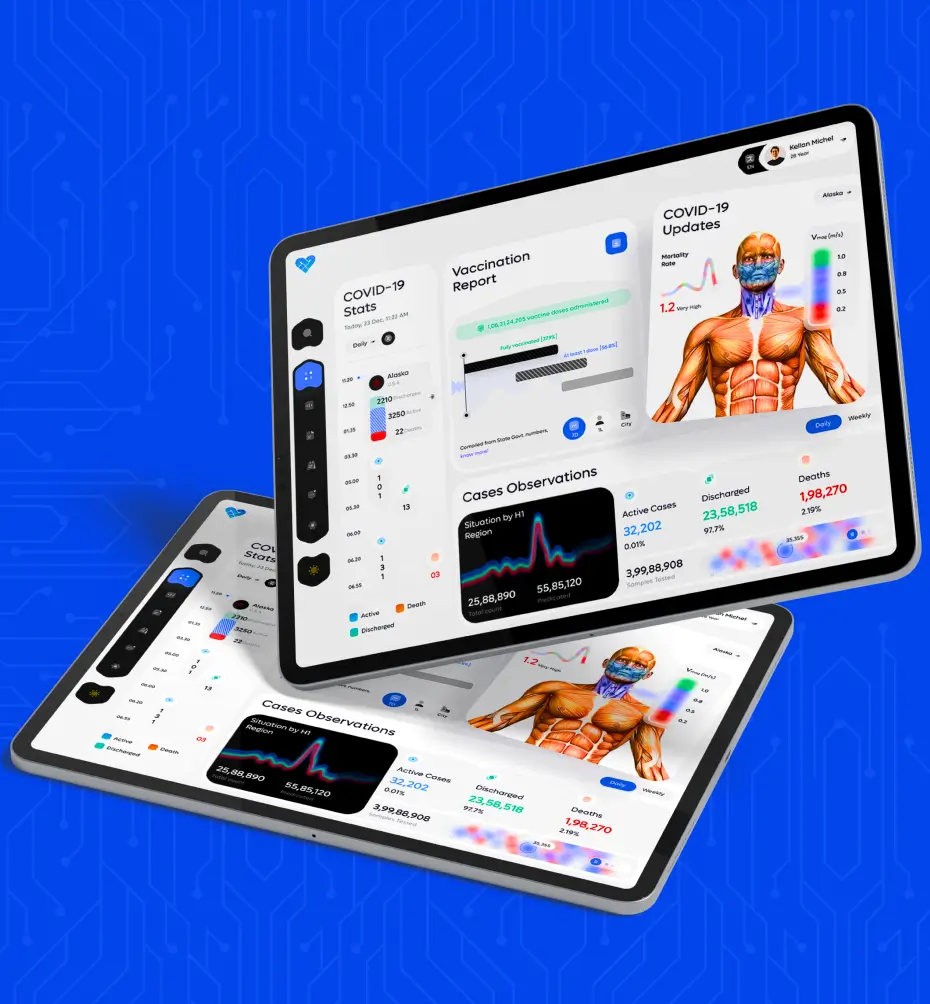

Astarte Medical

Creating software for Astarte Medical involves a meticulous process aimed at addressing their specific needs and objectives. It begins with thorough research and planning to understand the requirements goals of the project.

- Industry: Computer software

- Country: Germany, Issum

CAE Blue Phantom

CAE Blue Phantom is a cutting-edge simulation technology designed to revolutionize medical training and education. Utilizing advanced virtual reality and artificial intelligence, CAE Blue Phantom provides.

- Industry: Wellness & Fitness

- Country: Germany, Issum